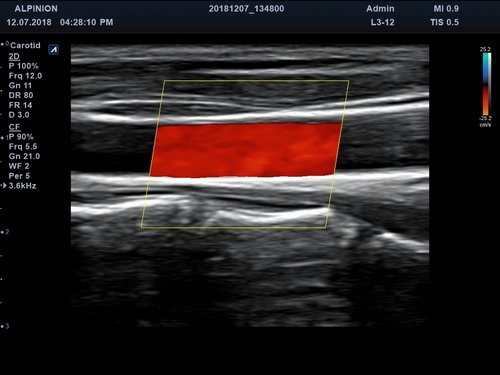

Anwendungsbereiche Abdomen MSK, Nerven, Karotis, periphere Gefäße, Schilddrüse, Mamma

Bildgebungs-Modi B-Modus, CF, M, PW, PD B-Modus, CF, M, PW, PD

• Farbdoppler: farbige Darstellung der Richtung des Blutflusses